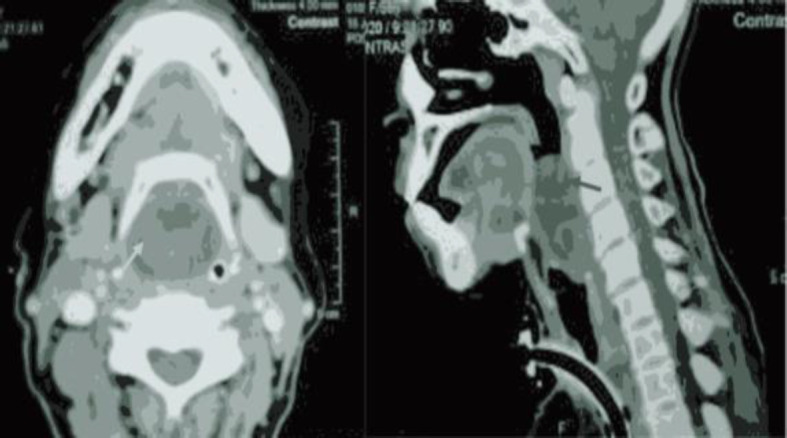

Case report: Here, a case of 56-year-old female is reported with chief complaints of severe progressive dyspnea and dysphagia. Diagnosis of schwannoma was confirmed on radiological and histopathological examination with certain hurdles. A complete surgical excision via endoscopic approach was done, revealing that the bottom of the mass was attached to the right arytenoid mucosa. The histopathological features showed non-malignant atypical neurofibroma but later confirmed as laryngeal schwannoma from immunohistochemical staining.